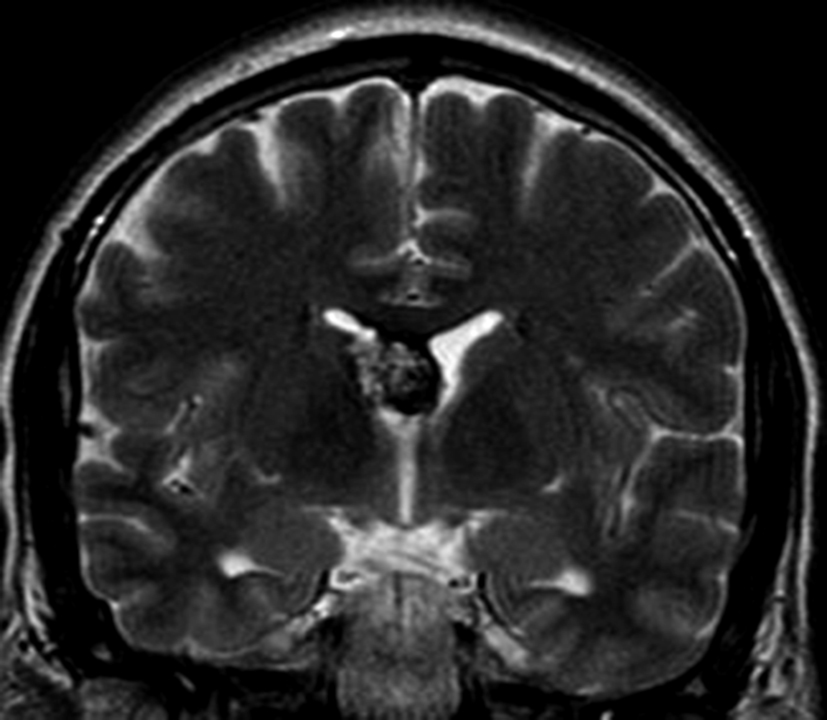

a y b) Imágenes coronales T2, Ay B. se evidencia la lesión con epicentro en el asta frontal del ventrículo lateral derecho y la extensión al cuero calloso.

Con los hallazgos tomográficos, no se efectúan planteos diagnósticos y se realiza una resonancia magnética con la finalidad de obtener más datos semiológicos en busca de una aproximación diagnóstica. Se realizó el estudio por medio de secuencias T 1, FSE T 2, FLAIR, SWI y Difusión, en cortes axiales, FSE coronal y sagital T 1. Se realiza la administración de gadolinio DTPA en los tres planos. Se evidencia la lesión bien definida a nivel del ventrículo lateral derecho, que involucra al tronco del cuerpo calloso (Figura 2- C y 3- B). Presenta intensidad de señal heterogénea en secuencias T1 y T2 (Figura 3 y Figura 4). En secuencia ecogradiente se observa una señal marcadamente hipointensa y heterogénea, con un halo hipointenso bien definido (Figura 2- C). No presenta realce significativo tras la administración de Gadolinio (Figura 2- B) y en la secuencia de difusión no presenta restricción.

Figura 4